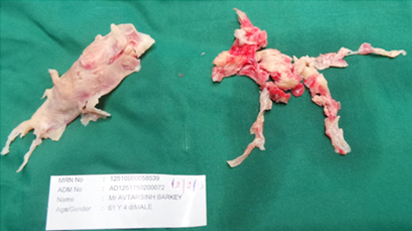

A surgical procedure called a pulmonary thromboendarterectomy is currently the recommended and only effective treatment for patients with CTEPH. During this complex procedure, the surgeon cleans out the blockages in the pulmonary arteries in the right and left lungs using specialized tools. The surgery is performed through a chest incision while the patient’s heart is stopped. A heart-lung machine takes over the function of the heart and lungs during the procedure.

Operative Specimen of Chronic Pulmonary Thrombus